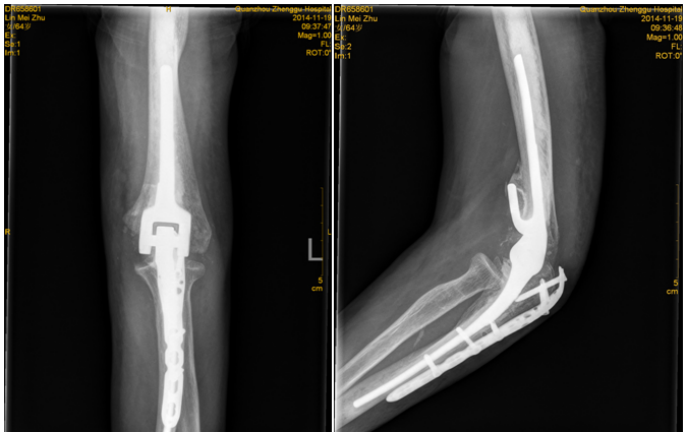

4.关节置换术

老年人关节内骨折合并骨质疏松症时,软骨下骨质量差,骨折块易嵌入关节面,解剖复位困难,骨折复位在下地负重或关节活动时难以维持,因此内固定治疗效果不佳。此时可酌情选择关节置换治疗,能够获得更好的预后。当骨折未累及关节面,但存在股骨头缺血性坏死风险时,例如股骨头下骨折或肱骨近端骨折,关节置换术的疗效于内固定[27][28][29]。随着反肩关节置换术的出现,越来越多的骨科医生选择关节置换术治疗复杂的肱骨近端骨折,获得了良好的治疗效果而肘关节置换术已成为复杂骨质疏松性肱骨远端骨折的常规治疗手段,临床研究也验证了其优良且可靠的治疗效果[28]。因此,当骨质疏松性骨折骨质量差,骨折碎片较小时,人工关节置换术应首先考虑。